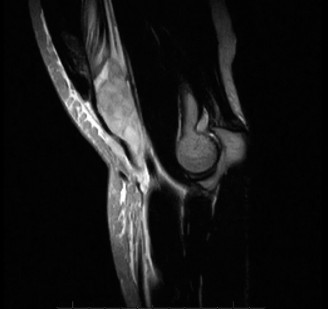

Treat a patient with scapular winging? CASE 23 A 47-year-old, right-hand-dominant male presents to your clinic complaining of right shoulder weakness for the past 2 months. He denies any history of trauma but notes sudden onset of pain 2 months ago that lasted approximately 2 weeks and then subsided without any intervention and was followed by shoulder weakness. He works as a lawyer and has been going through a divorce for the past year. Physical examination reveals no tenderness to palpation about the shoulder. He has decreased sensation over the lateral aspect of the shoulder, decreased muscle bulk over the left shoulder compared with the contralateral side, and weakness with left shoulder abduction. He is distally neurovascularly intact. The patient had already been referred for an x-ray and MRI by his primary care doctor that are shown in Figures 2–62 and 2–63.

Figure 2–62

Figure 2–63

The correct answer is (C). The patient’s decreased sensation over the deltoid, deltoid muscle atrophy on examination, and MRI with atrophy of the teres minor points to axillary nerve dysfunction. Suprascapular nerve injury (Choice A) would result in atrophy of the infraspinatus and or infraspinatus muscles, leading to weakness with external rotation and/or forward flexion. Dorsal scapular nerve injury (Choice B) would result in weakness of the rhomboid muscles and levator scapulae. While injury to the posterior cord of the brachial plexus (Choice D) would result in symptoms of axillary nerve palsy, they would also involve dysfunction of the radial nerve, which also comes off the posterior cord.

The correct answer is (B). Parsonage Turner syndrome (brachial neuritis) is characterized by acute brachial neuropathy which can affect different nerves of the brachial plexus. In this patient, it is the most likely explanation for his atraumatic deltoid paralysis with axillary nerve palsy in a time of severe stress. The cause of Parsonage Turner Syndrome is unknown, but it has been associated with severe stress and viral infection. Quadrilateral space syndrome (Choice A) involves entrapment of the axillary nerve as it passes through the quadrilateral space, would present as chronic dull pain, and is usually not associated with decreased sensation. While Choices C and D can both be a cause of axillary nerve injury, the patient has no history of trauma and there are no masses on his MRI.